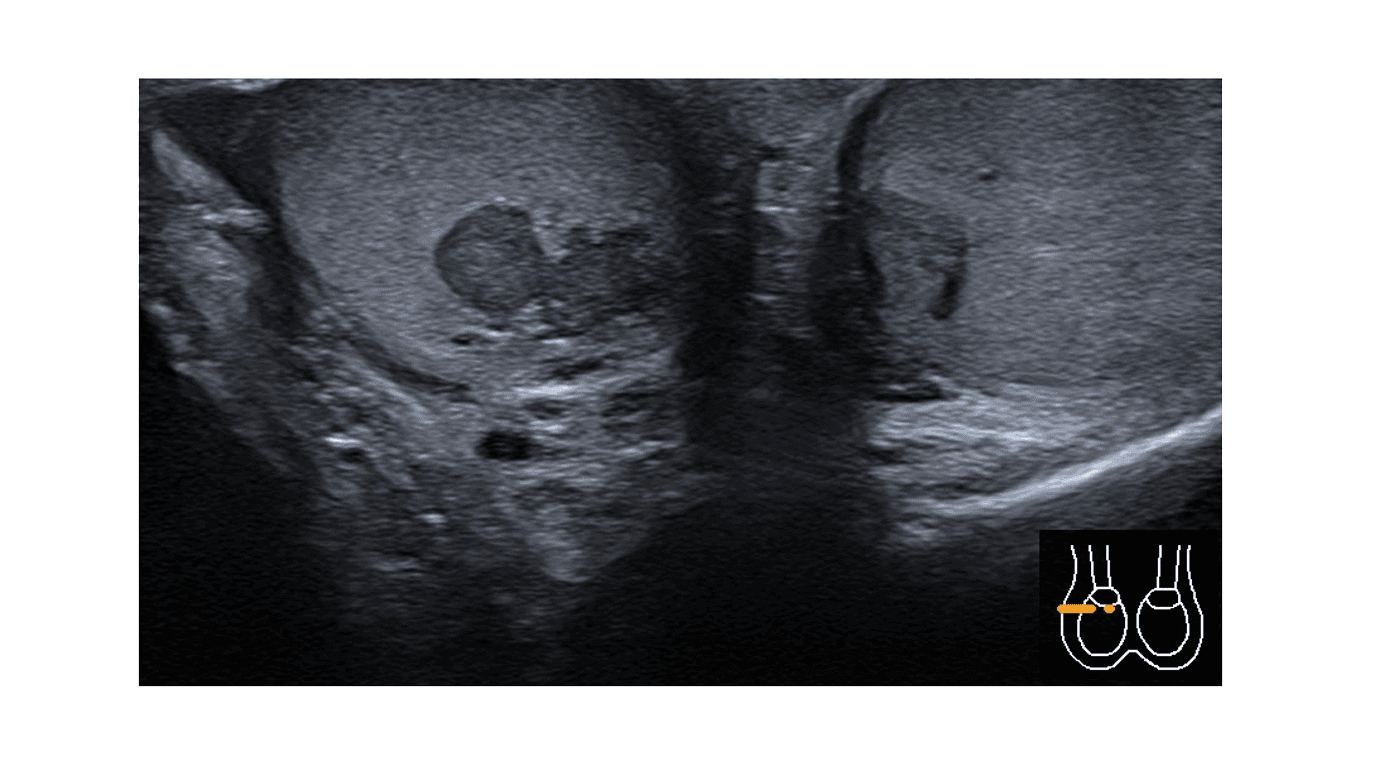

En mand i slutningen af 20’erne blev som tilflytter til kontrolforløb for kendt, klassisk AGS henvist til en lokal, endokrinologisk klinik. Han havde i længere perioder haft nedsat adhærens til behandlingen med hydrocortison og fludrocortisonacetat og havde flere indlæggelseskrævende episoder af akut binyrebarkinsufficiens bag sig. Undervejs fandtes biokemisk, hypogonadotrop hypogonadisme og let størrelsesreducerede testikler bilateralt. Ved ultralydundersøgelse (UL) af scrotum fandt man flere tumorer i testiklerne foreneligt med diagnosen testikel-binyre-resttumorer (testicular adrenal rest tumours, TART) (Figur 1). Efterfølgende forbedret adhærens til hydrocortisonbehandlingen normaliserede niveauerne af ACTH og androgene hormoner inkl. testosteron. Ved gentagne målinger blev der fundet normalt niveau af inhibin B, indikerende bevaret sertolicellefunktion og spermatogenese.

TART er godartede læsioner i testiklerne ved vedvarende forhøjet ACTH-niveau ved AGS, ofte forårsaget af underbehandling med hydrocortison. Fraværet af symptomer ved under- eller helt manglende behandling skyldes en vis, bevaret enzymaktivitet, og hos disse patienter opleves symptomatisk binyrebarkinsufficiens derfor først under interkurrent sygdom. TART antages at stamme fra pluripotente celler med karakteristika for både binyrebark- og Leydigceller, beliggende i testiklerne. TART findes, med betydelig usikkerhed på estimatet, hos ca. 40% af drenge og unge mænd med AGS [2]. Ved UL, der anbefales rutinemæssigt ved klassisk AGS, fremstår TART som typisk ensartede, bilaterale og velafgrænsede hypoekkogene læsioner beliggende nær mediastinum testis [3]. Disse karaktertræk er vigtige differentialdiagnostisk over for maligne læsioner, og for at undgå unødvendige biopsier og kirurgisk intervention [4].